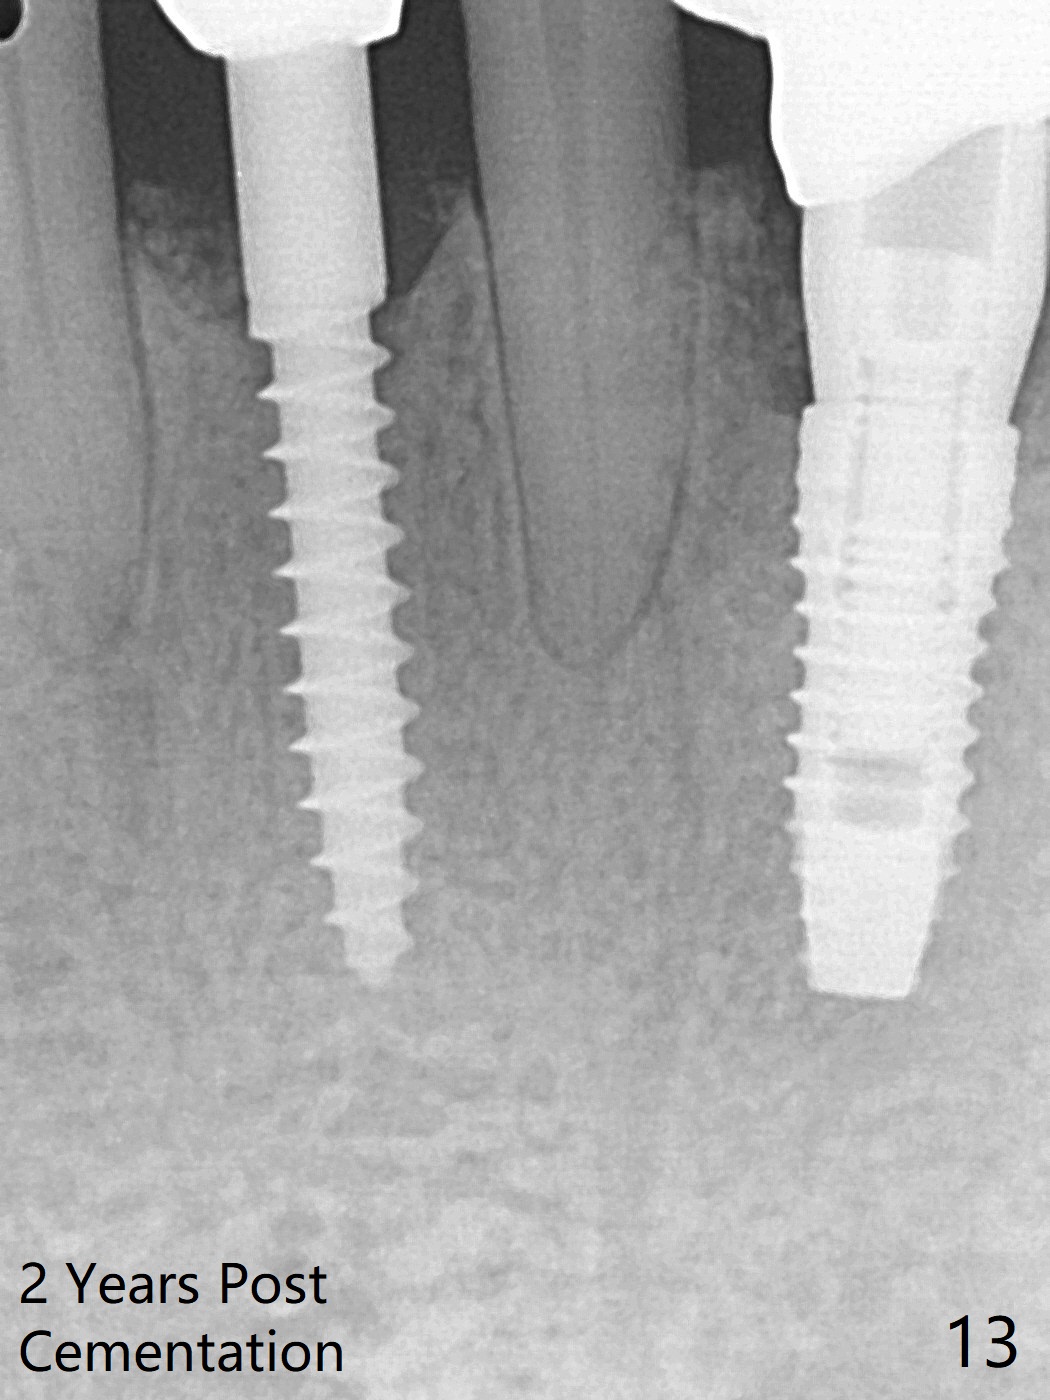

There is gingival inflammation at #25 buccally (Fig.1) and lingually (Fig.2). The bone loss is severe (Fig.3). Soft and hard tissue heights are 5 mm (cuff will be 4 mm) and 10 mm (implant will be 12 mm with 2 mm outside the native bone, Fig.4). The apex of the affected tooth appears deviated distal (Fig.5 *). The initial osteotomy happens to follow the long axis of the socket (Fig.6); to establish a correct trajectory, a new osteotomy should be made at the site labeled as a red line. In fact it is executed as planned (Fig.7). Because of the narrow flat ridge buccolingually, a 2.5x12(4) mm 1-piece implant is placed with >40 Ncm (Fig.8). With deeper placement of the implant, Vanilla graft is placed in 2 steps (Fig.9,10). The patient will return 2.5 months for extraction and implant of the fused teeth #22 and 23. No implant threads are exposed 10 months postop (Fig.11). CT taken 11 months postop shows that the 2.5 mm implant is in the middle of the bone (Fig.12) or 2 years post cementation (Fig.13).